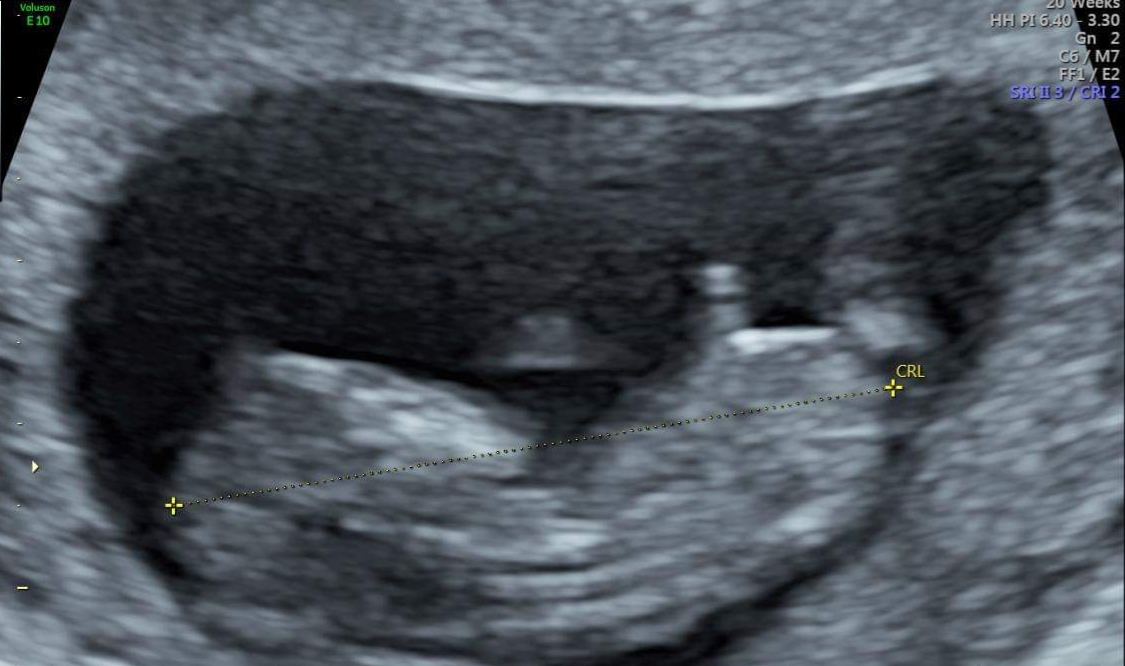

This was taken too early I understand at 10 plus 3. I am so convinced it looks like a boy though??

(I also had a scan at 11 + 4 yesterday but was told no nub was imaged).